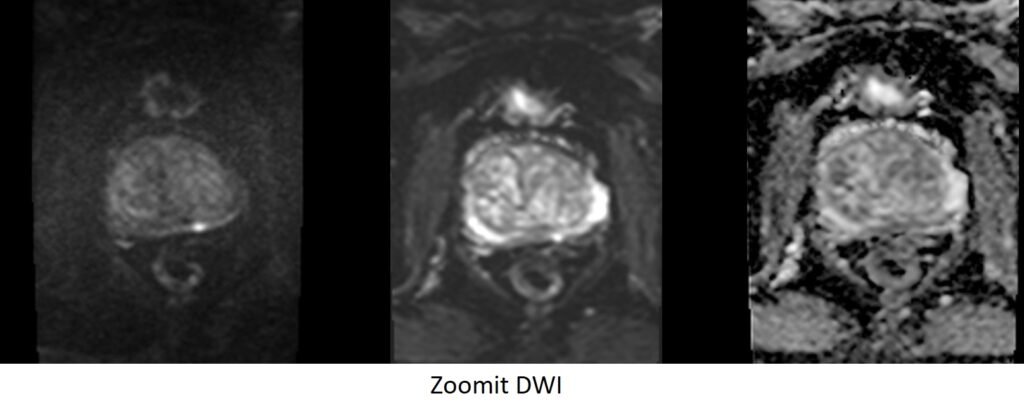

ZOOMIT DWI \ epi 4 scan trace axial 3 mm SFOV b50_b500_b800_1400

Plan the axial DWI block on the sagittal plane; angle the positioning block horizontally across the prostate (i.e., parallel to the base of the penis). Check the positioning block in the other two planes. An appropriate angle must be given in the coronal plane (parallel to the right and left femoral heads). Slices must be sufficient to cover the whole prostate and seminal vesicles. Additionally, to minimize artifacts arising from arterial pulsation, peristalsis, and breathing, consider incorporating saturation bands on top and in front of the axial block.

Parameters ZOOIT

TR 5000-6000 | TE 74 | FLIP 130 | NEX 10 | SLICE 3 MM | MATRIX 204X192 | FOV 200X110 | PHASE R>L | NSA 3 4 5 9 | B VALUE 0 |

Parameters EPI DWI

TR 5000-6000 | TE 110 | FLIP 130 | NEX 10 | SLICE 3 MM | MATRIX 192X192 | FOV 200-250 | PHASE R>L | NSA 3 4 5 9 | B VALUE 0 |

Zoomit DWI

Zoomit DWI is an advanced MRI imaging technique that leverages Siemens’ TimTX TrueShape platform and the application called Syngo ZOOMit. TimTX TrueShape introduces a new transmit platform with two independent transmitters, enabling flexible switching of RF waveforms and gradient shapes. This dynamic parallel transmission (pTX) capability opens up new possibilities for imaging applications.

Syngo ZOOMit, the first application based on TimTX TrueShape, utilizes the concept of “zooming” in MR imaging. Similar to optical zoom in a camera, ZOOMit allows for exciting a smaller field-of-view (FOV) than the object in the phase-encoding direction, thereby avoiding aliasing artifacts. By reducing the FOV, fewer phase-encoding lines are required, leading to faster scan times, improved spatial resolution in the region of interest, and reduced motion and flow artifacts.

Zoomit DWI offers several advantages over conventional DWI techniques. It employs multiple parallel radiofrequency pulse sequences simultaneously, capturing high signal specifically from the area of interest. This approach reduces folding artifacts, provides better anatomical detail, decreases distortion and blurring, and improves overall image quality. Additionally, it allows for faster screening, increased spatial resolution, and minimized susceptibility artifacts and geometric distortions.

With ZOOMit, radiologists and radiographers can selectively image the volume of interest, achieve faster and higher-resolution imaging, enhance diagnostic confidence by detecting and evaluating smaller lesions in challenging areas, and broaden the scope of clinical MR imaging.